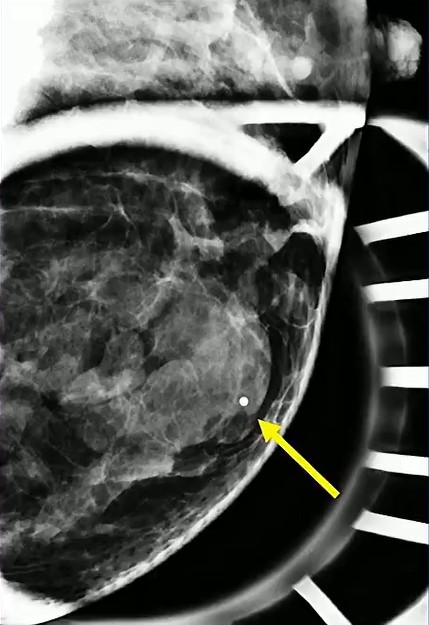

Solid Target: Physiologic lactational changes can introduce cystic elements, creating mixed solid–cystic morphology. When biopsy is indicated, precision matters: sampling the solid portion is essential to secure an accurate diagnosis and avoid false reassurance…as in the case of this 36-year-old postpartum patient (lump x 3 months) with biopsy-proved lactating adenoma.

Growth Raises Concern: Rapid enlargement should never be dismissed as purely hormonal. The differential remains broad, including phyllodes tumor, abscess, and malignancy.

In this case involving a 29-year-old patient with a quickly enlarging mass, biopsy confirmed a lactating adenoma—reinforcing that benign lesions can behave dramatically during pregnancy.